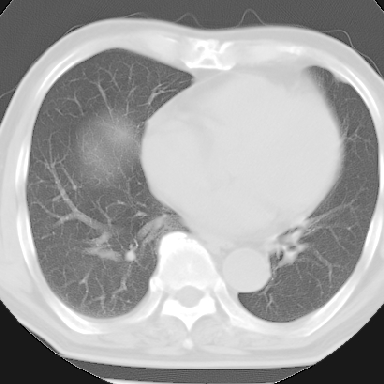

标题: CT8275:M 77 反复咳嗽咳痰10多年,慢性支气管炎请分析 [打印本页]

标题: CT8275:M 77 反复咳嗽咳痰10多年,慢性支气管炎请分析

m 77 反复咳嗽咳痰10多年,再发加重4天

纵隔窗呢?慢支炎肺气肿;余未见明显渗出及占位!

慢性支气管炎、肺气肿。

不支持慢性支气管炎,另外慢性支气管炎的诊断需结合临床病史才能诊断。

这份病例诊断慢支并气肿可能属过诊,首先慢支的临床诊断标准是严格的,应该弄清楚,其次ct表现是否符合该病表现,本例老年人ct肺窗表现应属正常,不要跟着临床跑。